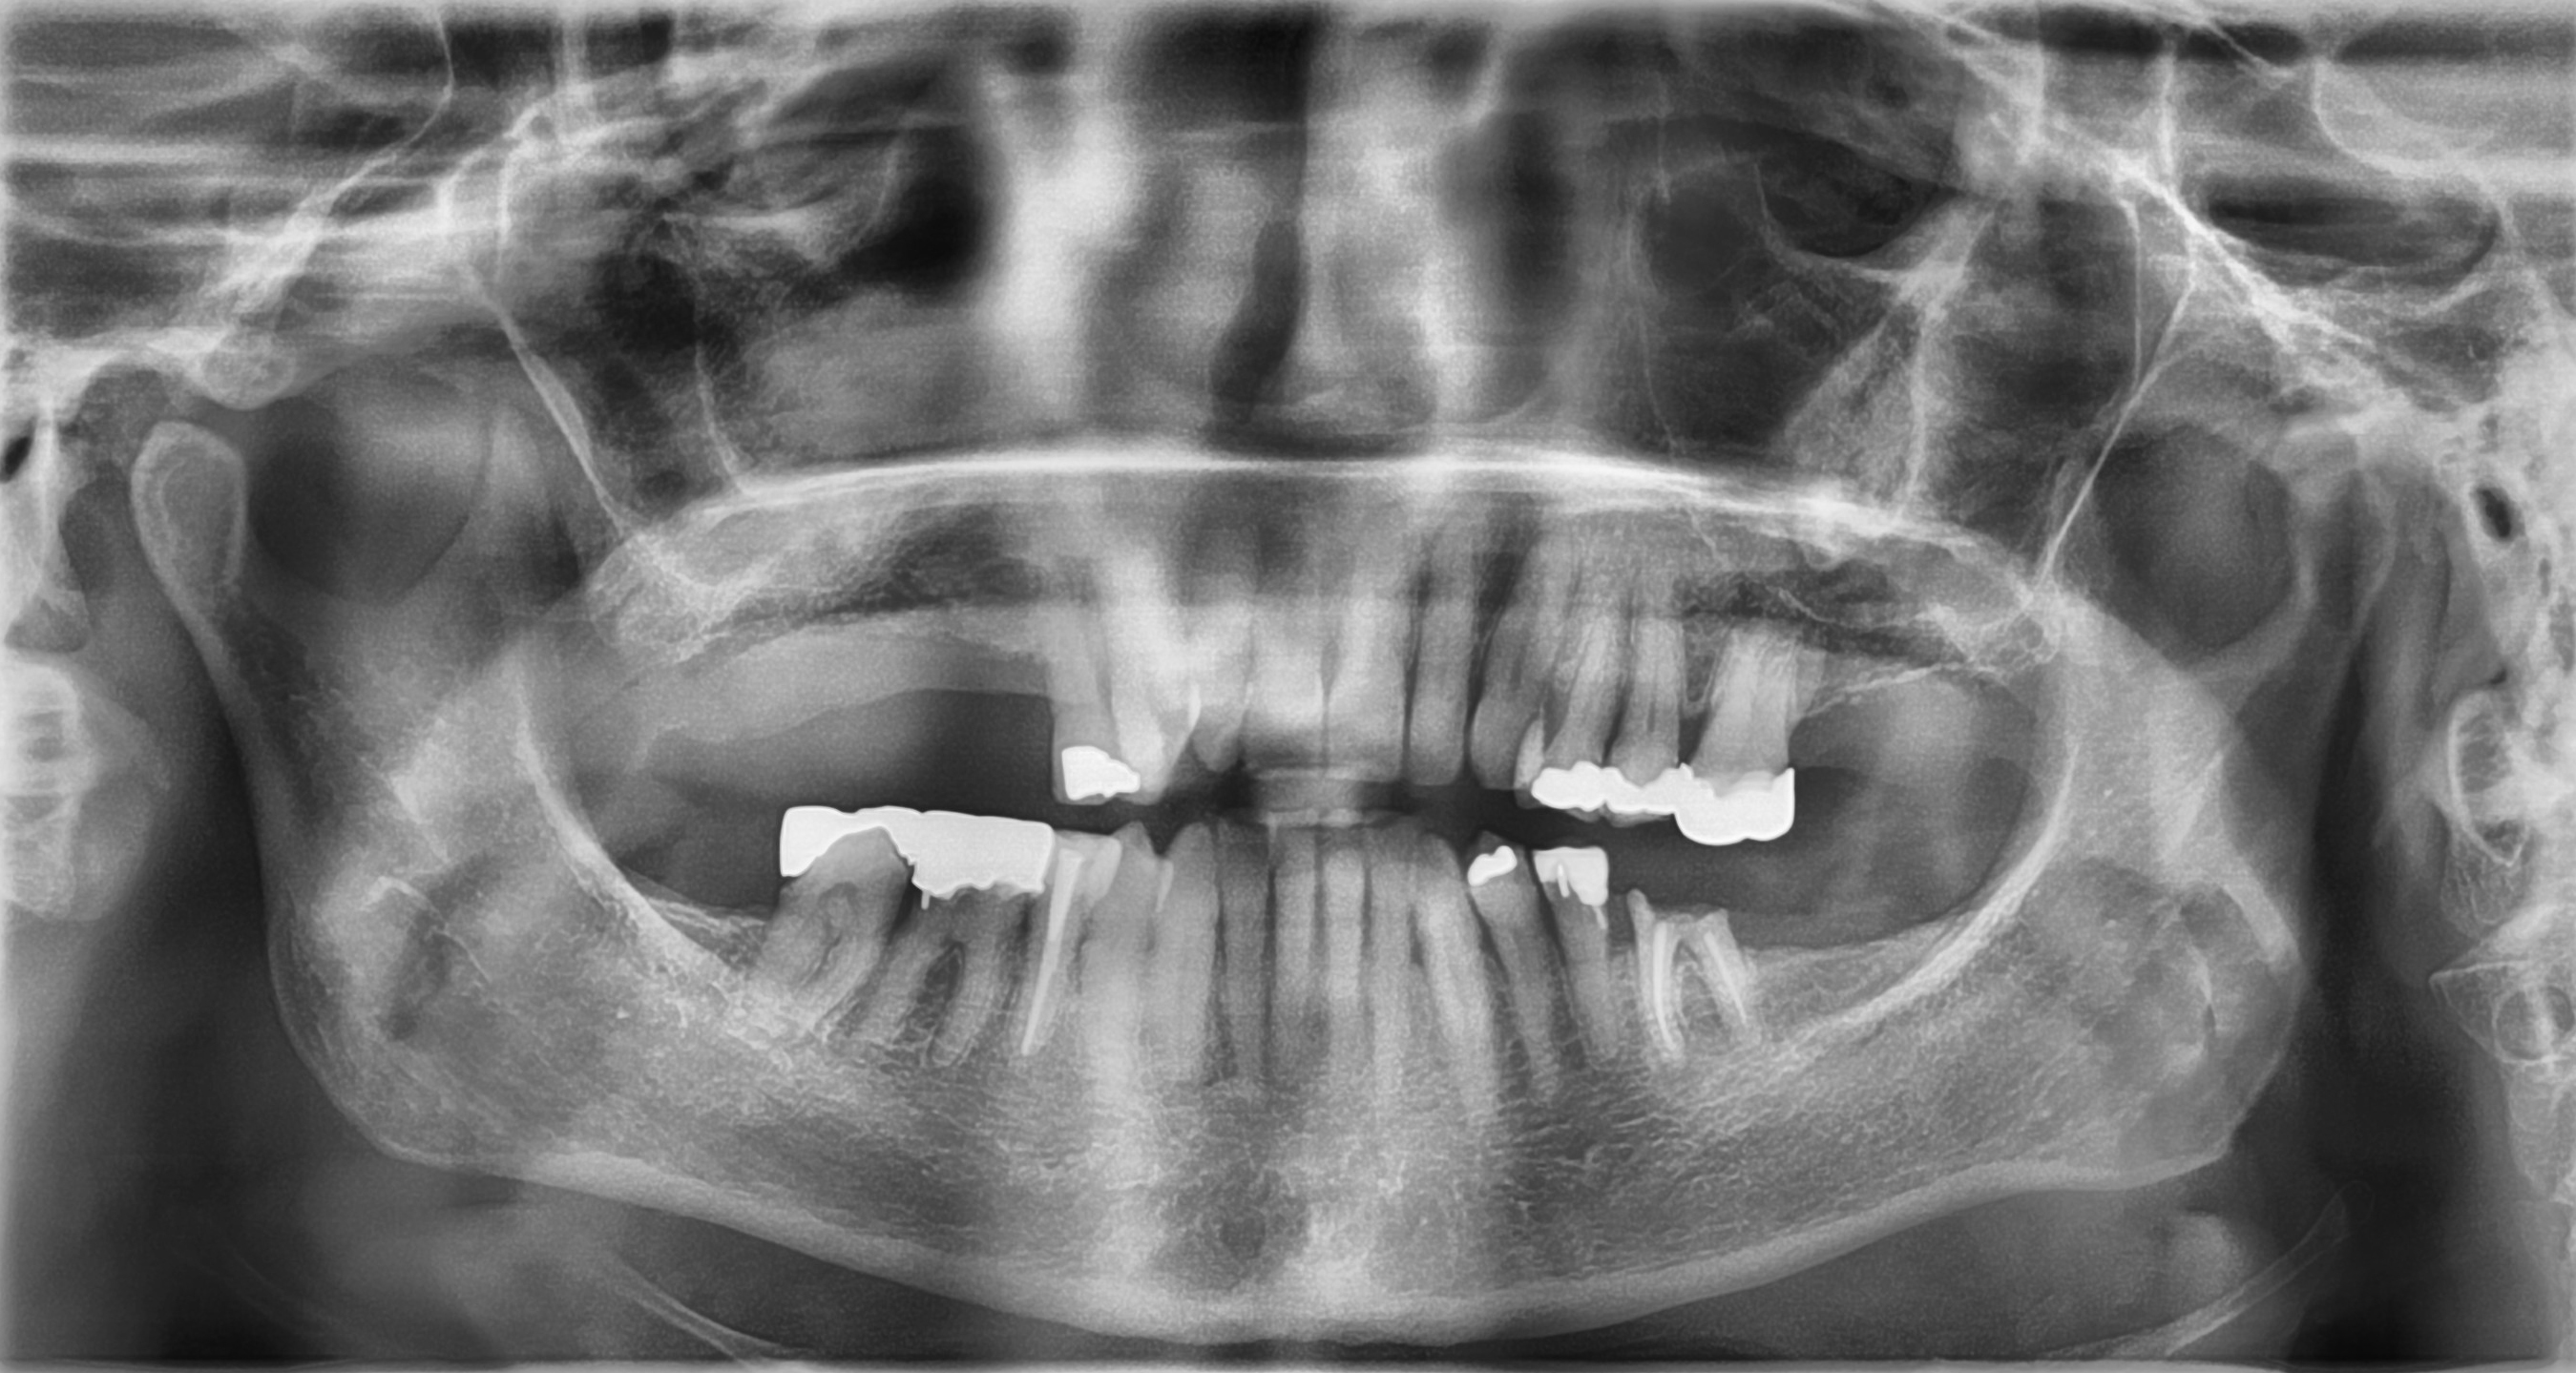

Fig. 2: Pre-op radiographic assessment.

A 64-year-old female patient presented to our practice with a heavily restored dentition. Her failing maxillary right first molar and second premolar had been extracted by her general dental practitioner (Fig. 1), leaving an unbounded edentulous area. Radiographic assessment indicated that there was ample bone depth in the posterior maxilla to allow for satisfactory implant placement (Fig. 2). An implant solution was provided using two individual screw-retained crowns supported by two OmniTaper EV implants (Dentsply Sirona) and using a digital workflow with Primescan and Atlantis (Dentsply Sirona).